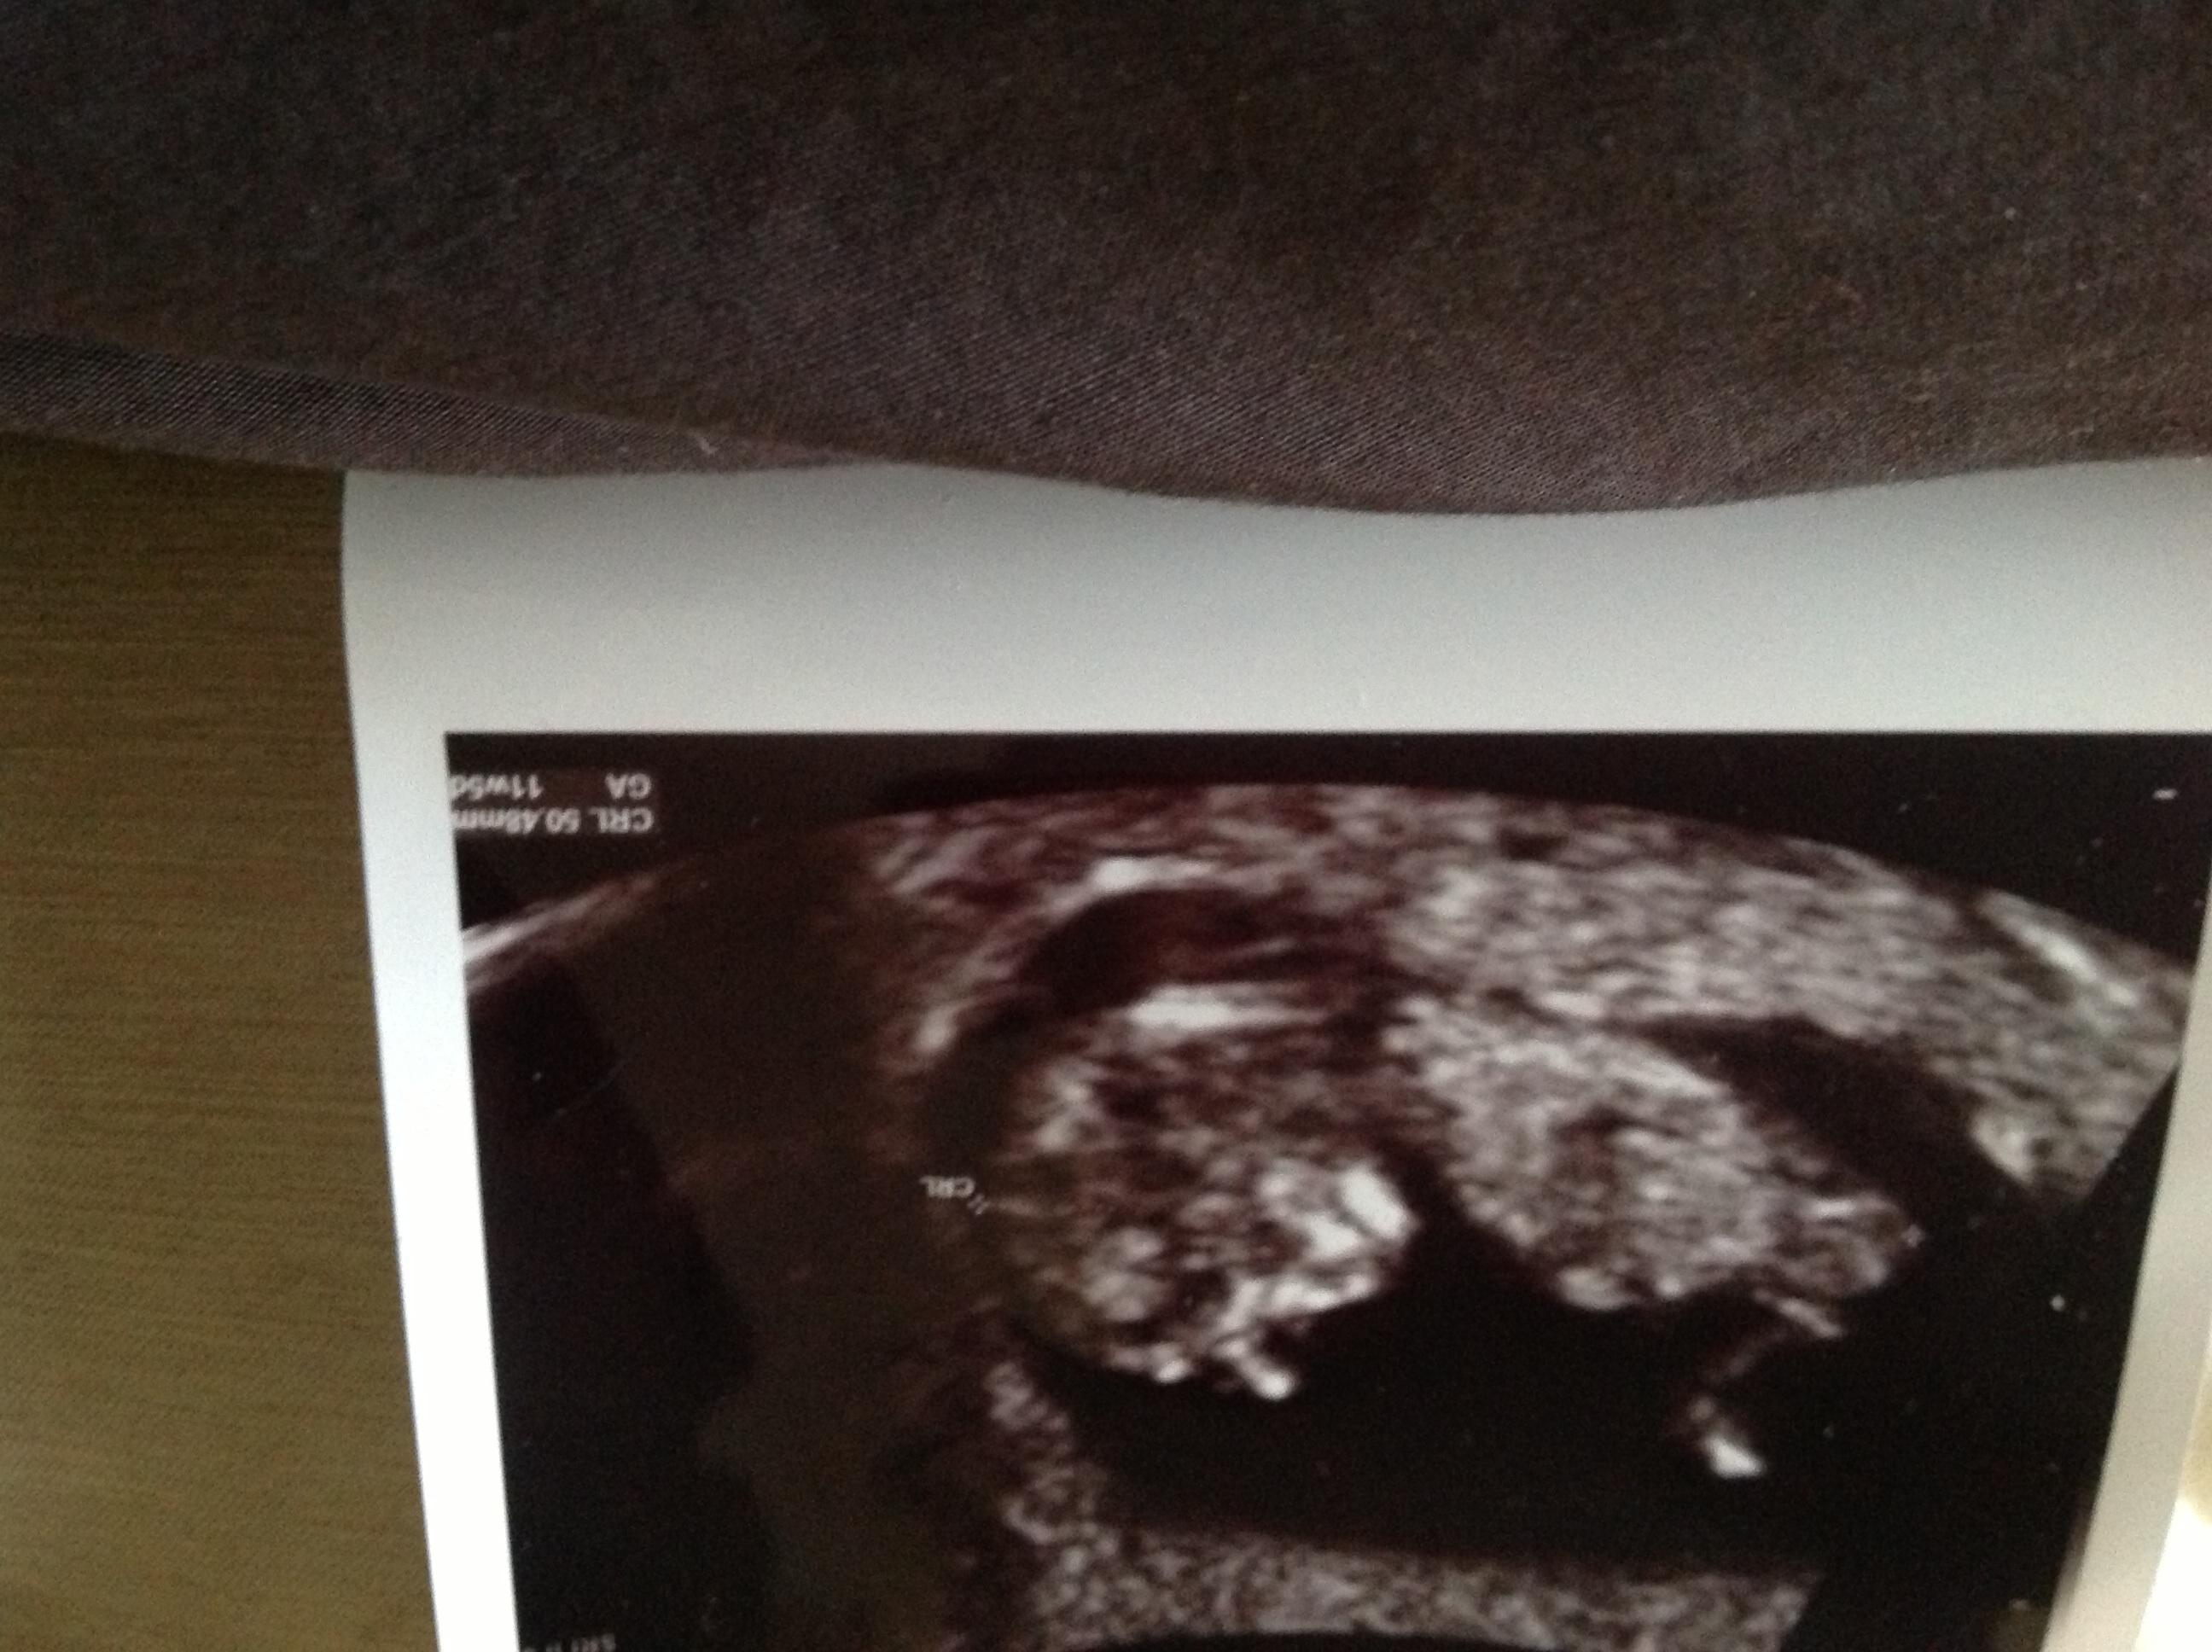

This is at 11wks 5 days so still v early- I have 2 boys so am convinced its a boy yet desperate for a girl, I'm driving myself insane....Attachment 14850